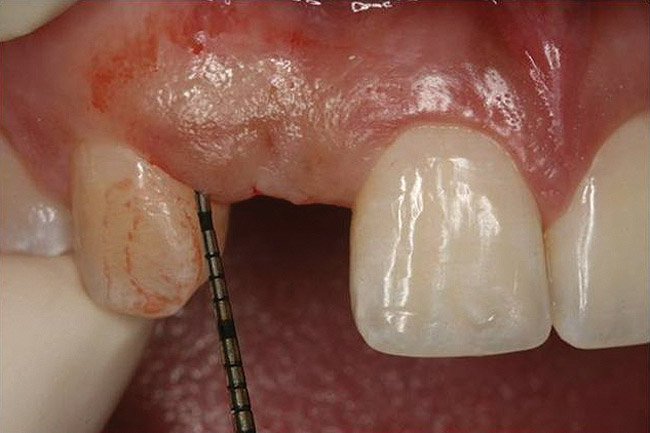

Figure 10 Clinical examination of the bound edentulous space: Measurement of the distal (Fig 10) and mesial (Fig 11) interproximal tissue height using a periodontal probe supplements data obtained from the periapical radiograph. Estimation of the buccal t

Figure 10

Figure 11 Clinical examination of the bound edentulous space: Measurement of the distal (Fig 10) and mesial (Fig 11) interproximal tissue height using a periodontal probe supplements data obtained from the periapical radiograph. Estimation of the buccal t

Figure 11

Figure 12 Clinical examination of the bound edentulous space: Measurement of the distal (Fig 10) and mesial (Fig 11) interproximal tissue height using a periodontal probe supplements data obtained from the periapical radiograph. Estimation of the buccal t

Figure 12

Dental implant treatment planning must focus on the architecture of the bound edentulous space. This may be divided into two separate areas of concern. As mentioned above, one is the condition of the adjacent teeth and, in particular, the level of connective tissue attachment that determines the ultimate location of papilla at the single-implant crown (Figure 10 and Figure 11). The other is the condition of the alveolus within the bound edentulous space. The extent of resorption in the vertical and horizontal direction must be considered (Figure 12). There exist several classification systems for this (eg, Seibert, Allen) that identify the presence or extent of alveolar and horizontal alveolar bone deficiency. Pragmatically, clinical resolution requires that the position of the planned implant crown be identified in the context of the alveolar bone (discussed below).